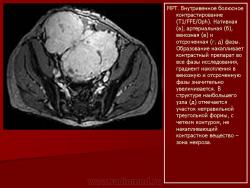

Онкология. Фибросаркома забрюшинного пространства. +

Фибросаркома забрюшинного пространства.